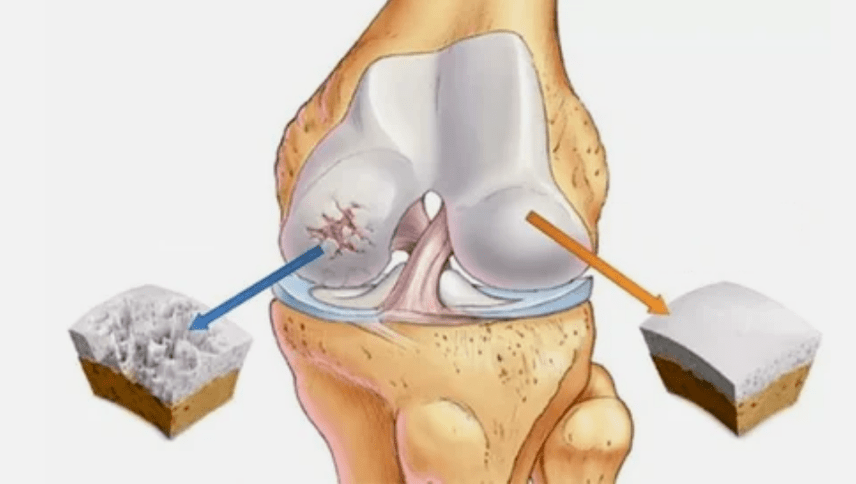

- The primary lesion affects the hyaline cartilage.In the case of circulatory disorders, there is a deterioration in the pathological force.It is the first step or the first cause that arthrosis can occur.

- Hyalin coating pathologies.The thinning of the cartilage leads to the replacement of its pathological tissue - bone structures.

- Anomal growth appear on cartilage - osteophytes.

- The occurring violation of the natural anatomy of the cartilage and bones leads to the overload of healthy cartilage areas.The destruction of joint tissues without treatment continues to lead and leads to disabilities.

If the degree of illness increases, pathological processes are still worse.In the end, the entire hyalink norp is destroyed.